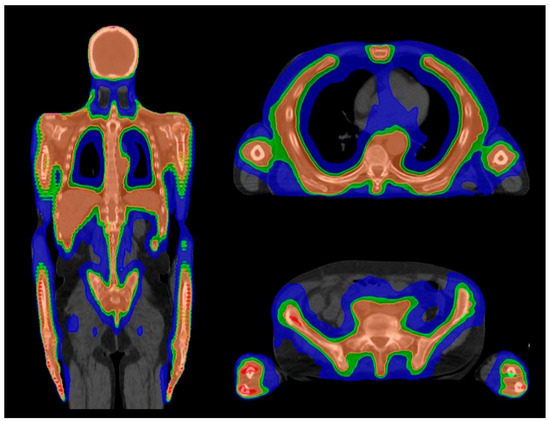

4.1. Planning

| Organ at Risk | TBI Median Doses (Gy) | Studies Evaluating TMI/TMLI Median Doses (Gy) | ||

|---|---|---|---|---|

| Wong et al. [51] (TBI 12 Gy) | Wong et al. [51] (TMI/TMLI 12 Gy) | Wong et al. [51] (TMI/TMLI 20 Gy) | Our Case (TMLI 12 Gy) | |

| Brain | 12.0 | 4.0 | 7.9 | - |

| Lens | 11.3 | 1.5 | 1.9 | 1.7 |

| Eyes | 11.3 | 6.6 | 7.0 | 5.7 |

| Optic nerves | 12.4 | - | - | - |

| Oral cavity | 11.8 | 3.9 | 4.8 | 8.5 |

| Parotids | 11.8 | 3.9 | 4.8 | 9 |

| Thyroid | 12.1 | 3.7 | 4.9 | 3.9 |

| Esophagus | 12.4 | 3.9 | 5.6 | 11.7 |

| Breasts | 11.5 | 6.9 | 8.7 | - |

| Lungs | 8.9 | 4.3 | 6.8 | 7.7 |

| Heart | 12.1 | 6.2 | 6.4 | 6.1 |

| Stomach | 12.2 | 3.1 | 5.0 | 5.5 |

| Small Intestine | 12.5 | - | - | 5.7 |

| Liver | 12.3 | 6.0 | 8.7 | - |

| Kidneys | 12.2 | 5.6 | 8.7 | 5 |

| Bladder | 12.4 | 7.0 | 7.4 | 6 |

| Rectum | 12.6 | - | - | 5.9 |